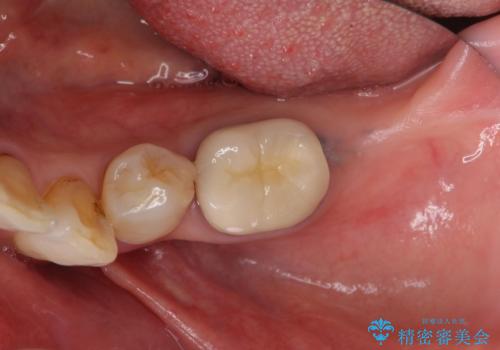

70代女性 段差のある被せ物のやり替え

- 左下の大臼歯(6番)の根の治療を行いました。

後方の歯が欠損していた為、インプラントをお勧めしましたが希望されませんでした。

その代わり、現在ある歯をしっかり治療することになり、左上下の治療を行っています。